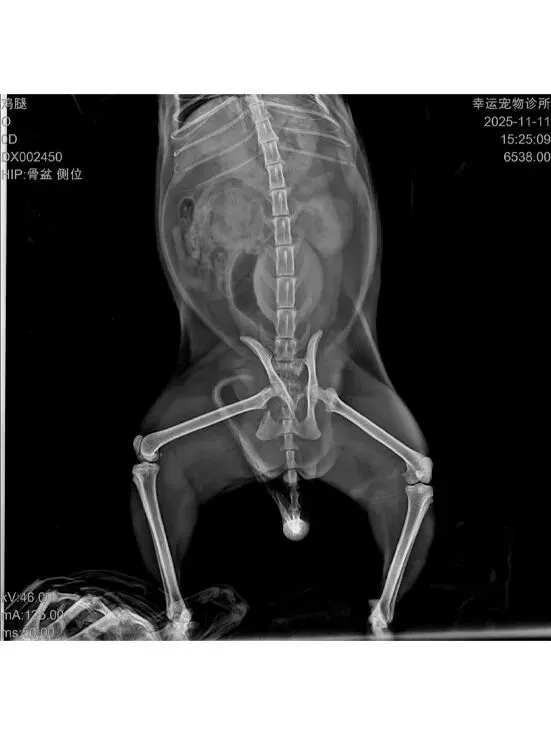

志愿者发现鸡腿蜷缩在楼梯底下不断嚎叫,且后腿无法动弹,于是当天抓捕送医。

就医检查:鸡腿后肢在医生被触摸时仍有痛觉反应,经判断大概率为盆骨骨折,且右后脚带有明显伤口,具体情况需拍摄X光片来确定。鸡腿连袋重:4.95kg。

盆骨X光片:盆骨粉碎性骨折,因十号的生化血常规和SAA指标达标,于是准备12号进行手术。